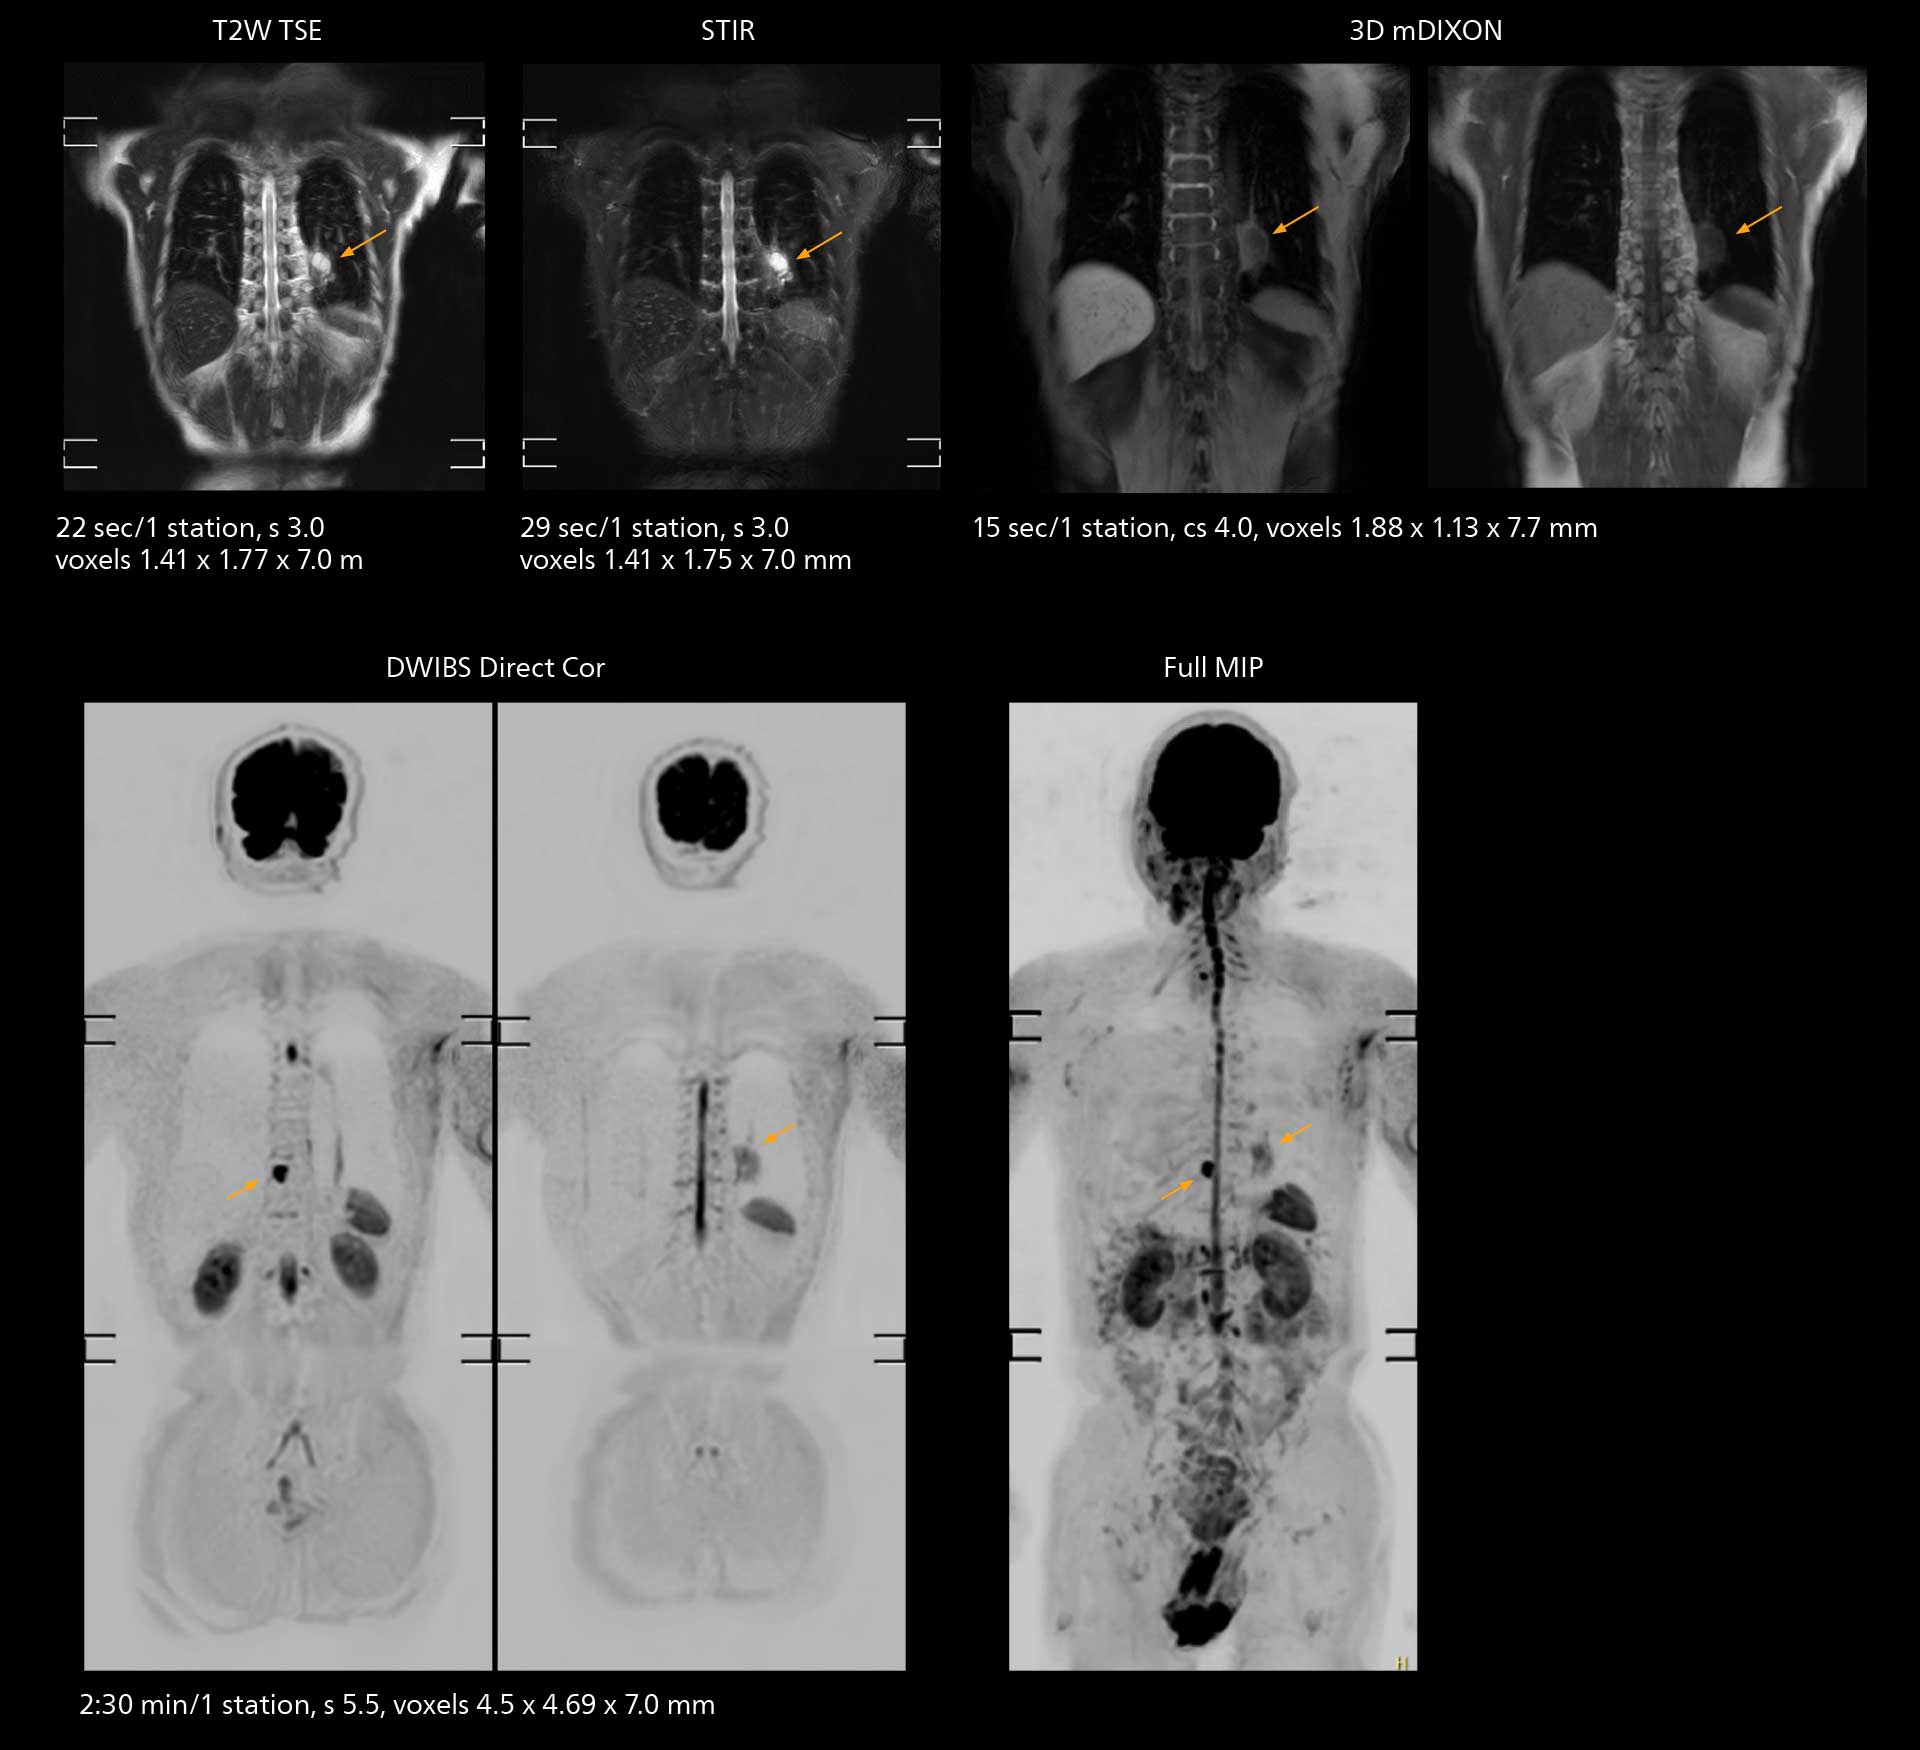

The value of the Elition X gradients is also evident in DWIBS studies. “The fact that we can consistently obtain distortion‐free DWIBS while reducing imaging time at three coronal stations is excellent,” Dr. Makuuchi says. “In these patients, it’s also important that the application of Compressed SENSE to T2‐weighted, STIR and mDIXON sequences has no impact on the examination time of whole‐body imaging. As a result of the increased speed and higher image quality we realize, DWIBS studies have now become routine examinations.”

With SmartPath to Elition X the team can obtain excellent quality DWIBS imaging and reduce imaging time. Other sequences also fit in the examination slot. This case shows left paravertebral neurogenic tumor and Th10 vertebral hemangiomas.